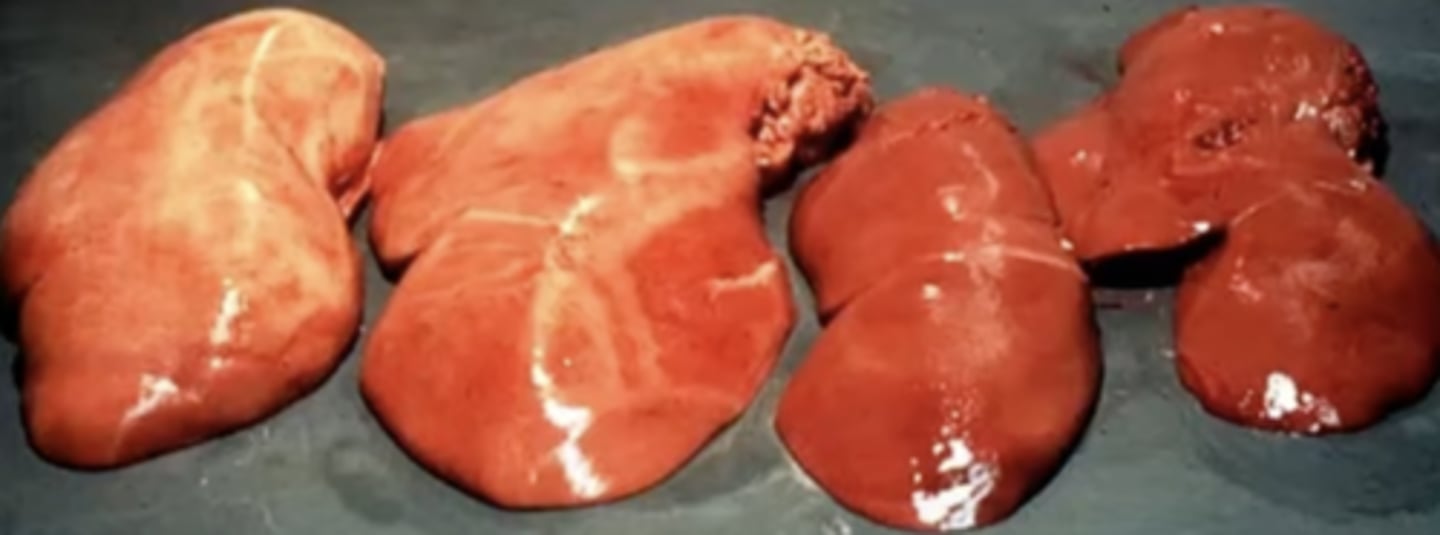

Hepatic lipidosis

Cat liver: What is wrong here?

Hyperlipemia

Pony liver: What caused this gross appearance?

Fatty liver- caused by hepatocellular steatosis (lipidosis)

Monkey liver: What caused this gross appearance?

Bovine Fatty Liver Syndrome

- Caused by accumulation of lipid within the liver due to increased mobiliazation of lipids from adipose tissue = influx of fatty acids to the liver

Bovine liver: What has caused this gross appearance ?